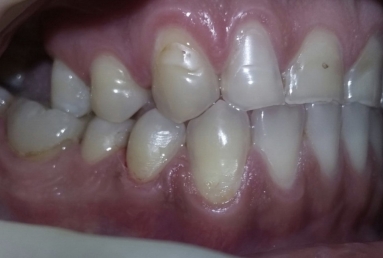

This patient has advanced dental abrasion due to bruxism ( clenching the teeth during the night). this is why the bite is modified and the frontal teeth are shorter. First stage of the treatment is wearing a night guard to relax the muscles and the temporo-mandibular jaw.

Then fixed orthodontic treatment is set for almost 2 years, so moving the teeth a new more favorable position is obtained to create space for veneers. After wax up a mock up is done for provisional veneers and the new occlusion is tested.